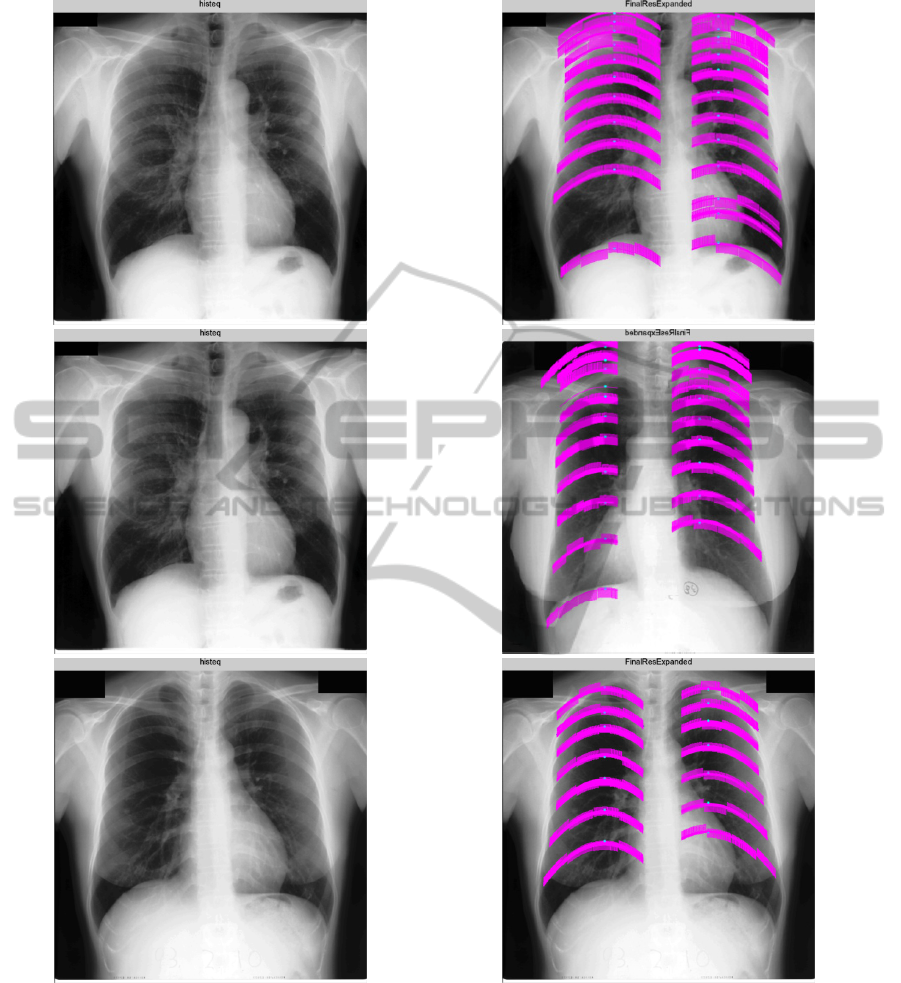

cover all ribs in the ribcage or report incorrectly

some other curves that resembles a rib boundary.

Since the present method does not require the

detection of any border but only its outmost starting

point, the detection rate can be substantially

increased by log Gabor filtering approach. Second

contribution is a new region growing technique that

is introduced to extend rib center to build the entire

rib until rib boundaries are reached. The technique

allows each individual rib to grow independently

from its initial parabola equation. In that sense, the

difference between the curvative structure of upper

and lower ribs can be elaborated. Based on the

visual examinations of a common dataset of lung

images, we can argue that the results are very

promising to continue with a suppression method

that follows the rib delineation.